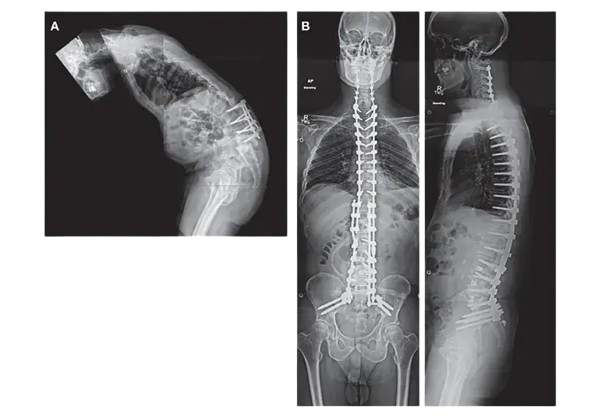

Deformity Surgery

Deformity surgery corrects abnormal bone alignment and skeletal deformities caused by congenital conditions, trauma, or disease.

These procedures restore alignment, improve posture, reduce pain, and enhance mobility.